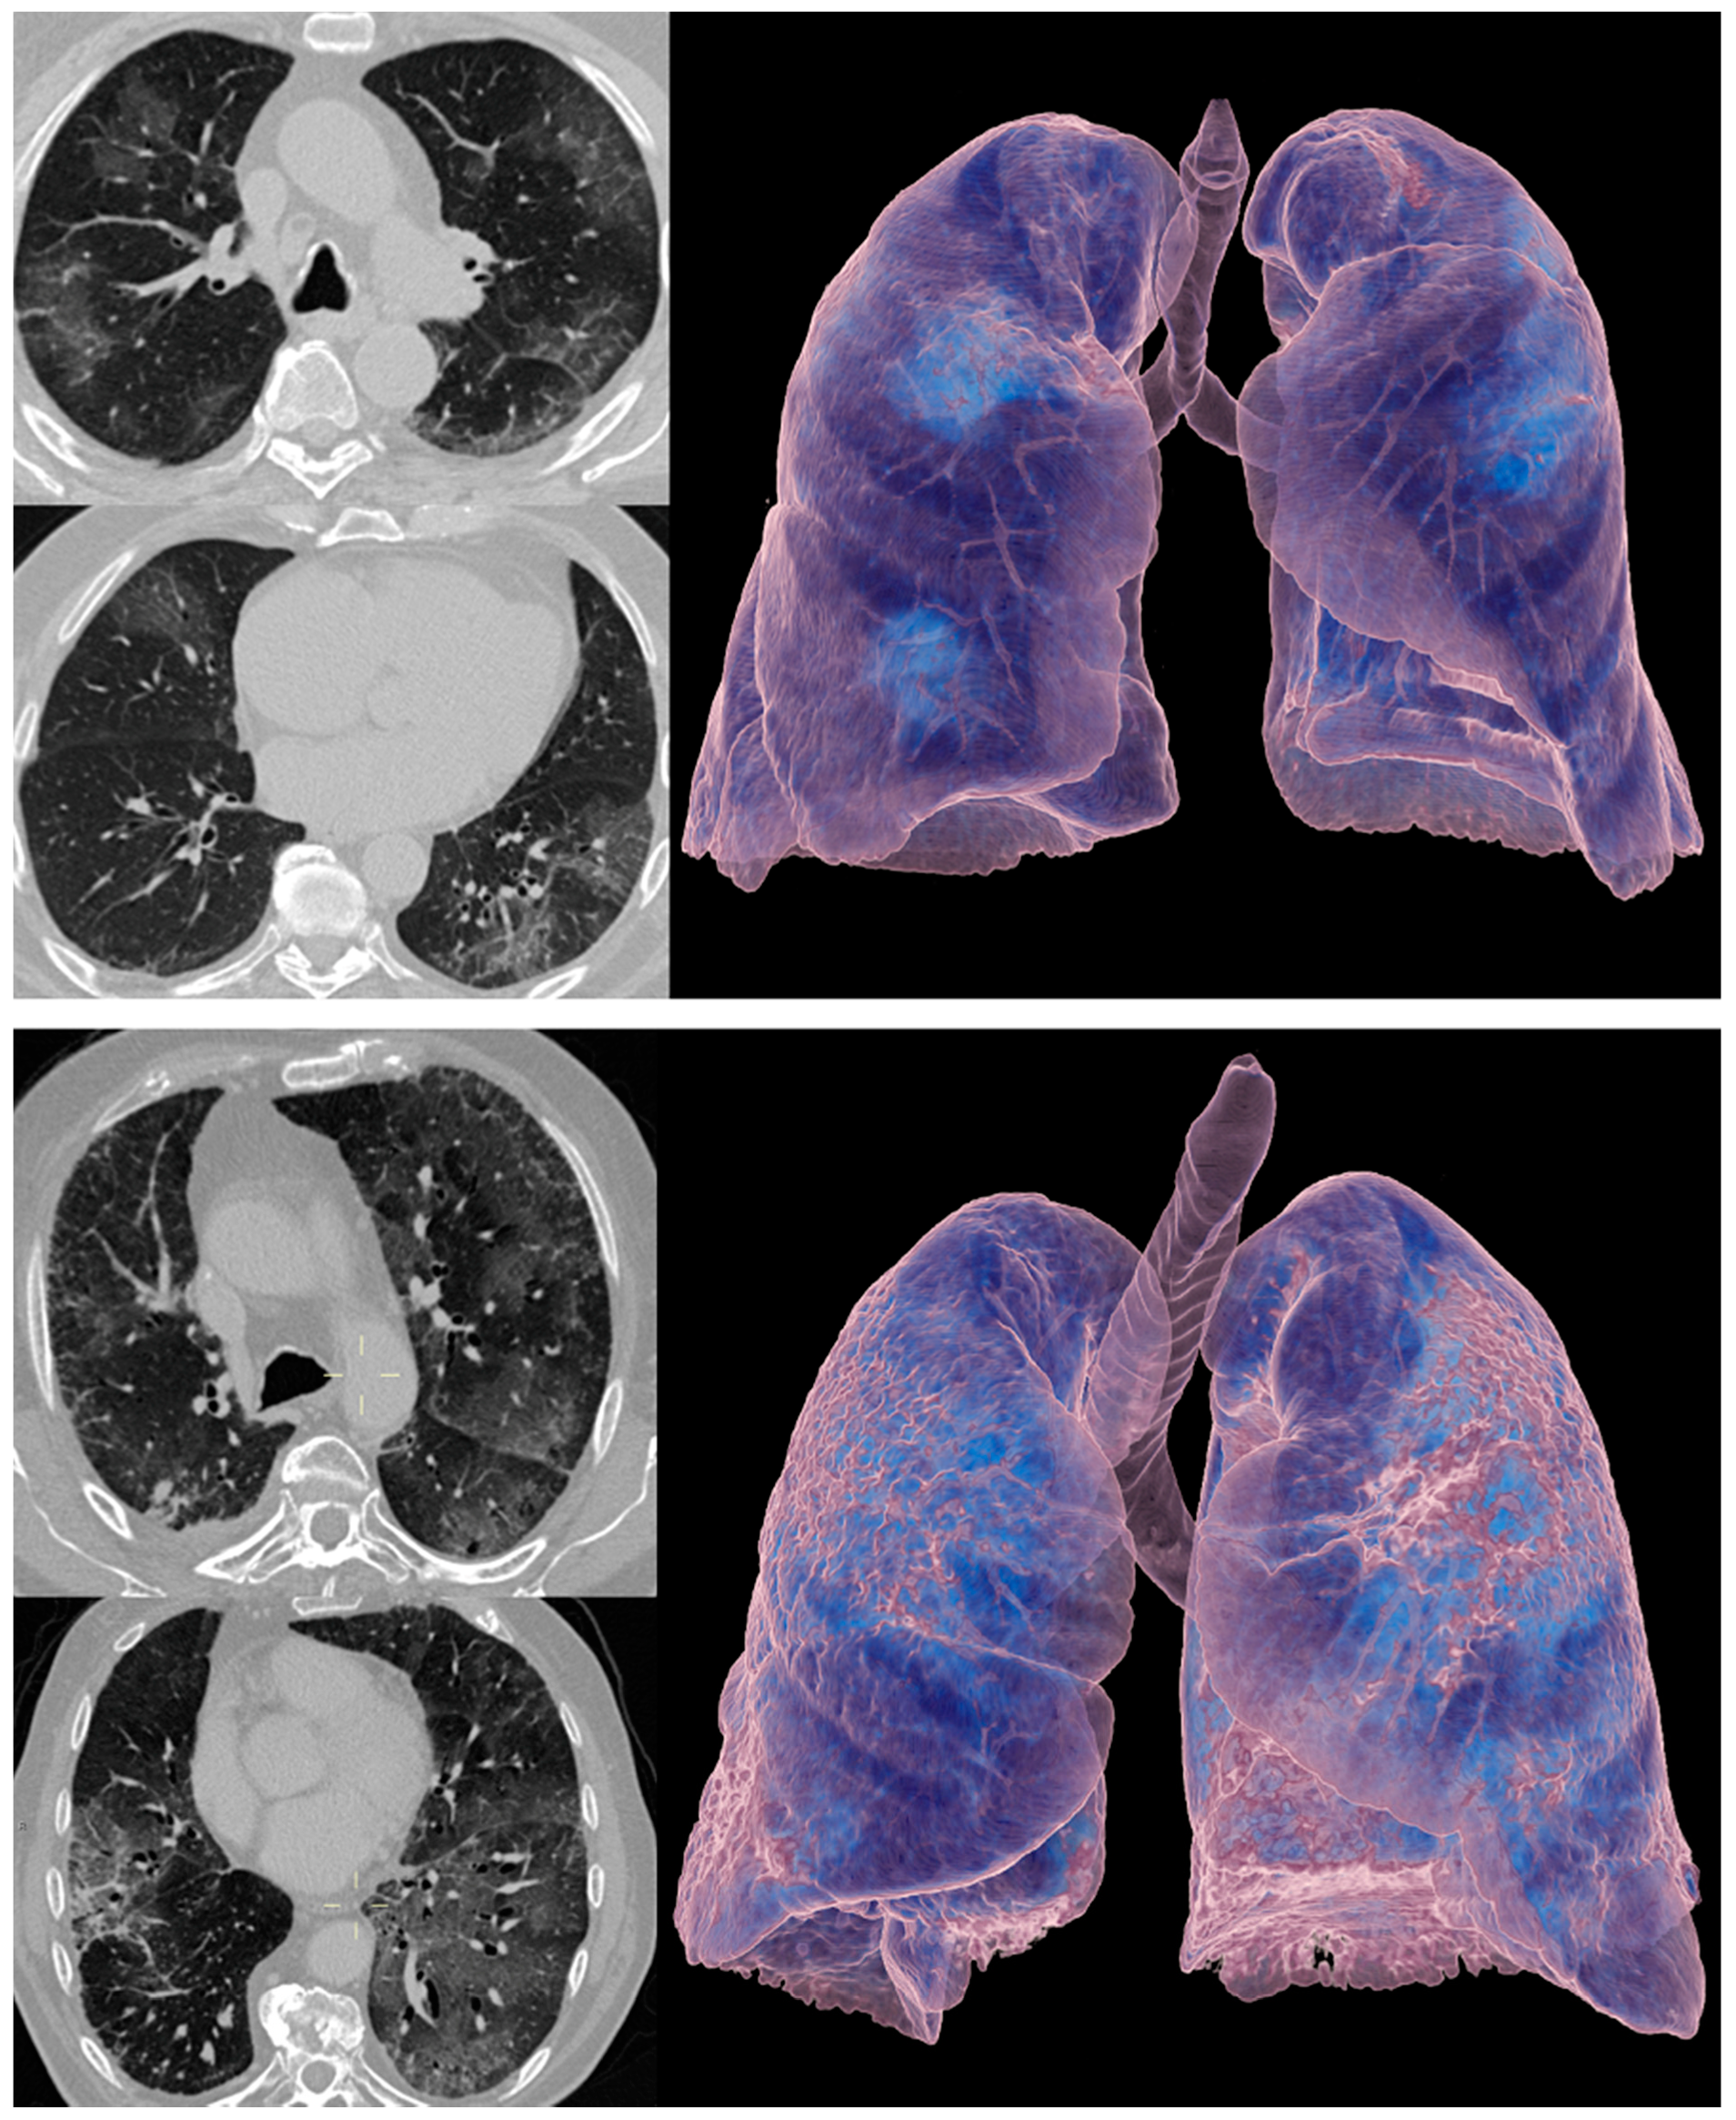

Representative CT images are shown in Figure 3.

Figure 3.

Computed tomography (CT) images of patients with RT-PCR-proven COVID-19 pneumonia (upper panel) and ICI therapy-related pneumonitis (lower panel). Axial CT images with lung window (left side of upper and lower panel) and 3D volume rendering technique (VRT) images (right side of upper and lower panel) are shown. Note the overlapping CT features of ground-glass opacities between the two cases of different etiology.